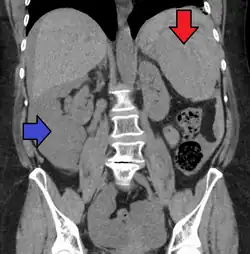

Splenic rupture is usually evaluated by FAST ultrasound of the abdomen.[5] Generally this is not specific to splenic injury; however, it is useful to determine the presence of free floating blood in the peritoneum.[5] A diagnostic peritoneal lavage, while not ideal, may be used to evaluate the presence of internal bleeding a person who is hemodynamically unstable.[6] The FAST exam typically serves to evaluate the need to perform a CT scan.[6] Computed tomography with IV contrast is the preferred imaging study as it can provide high quality images of the full peritoneal cavity.[5]